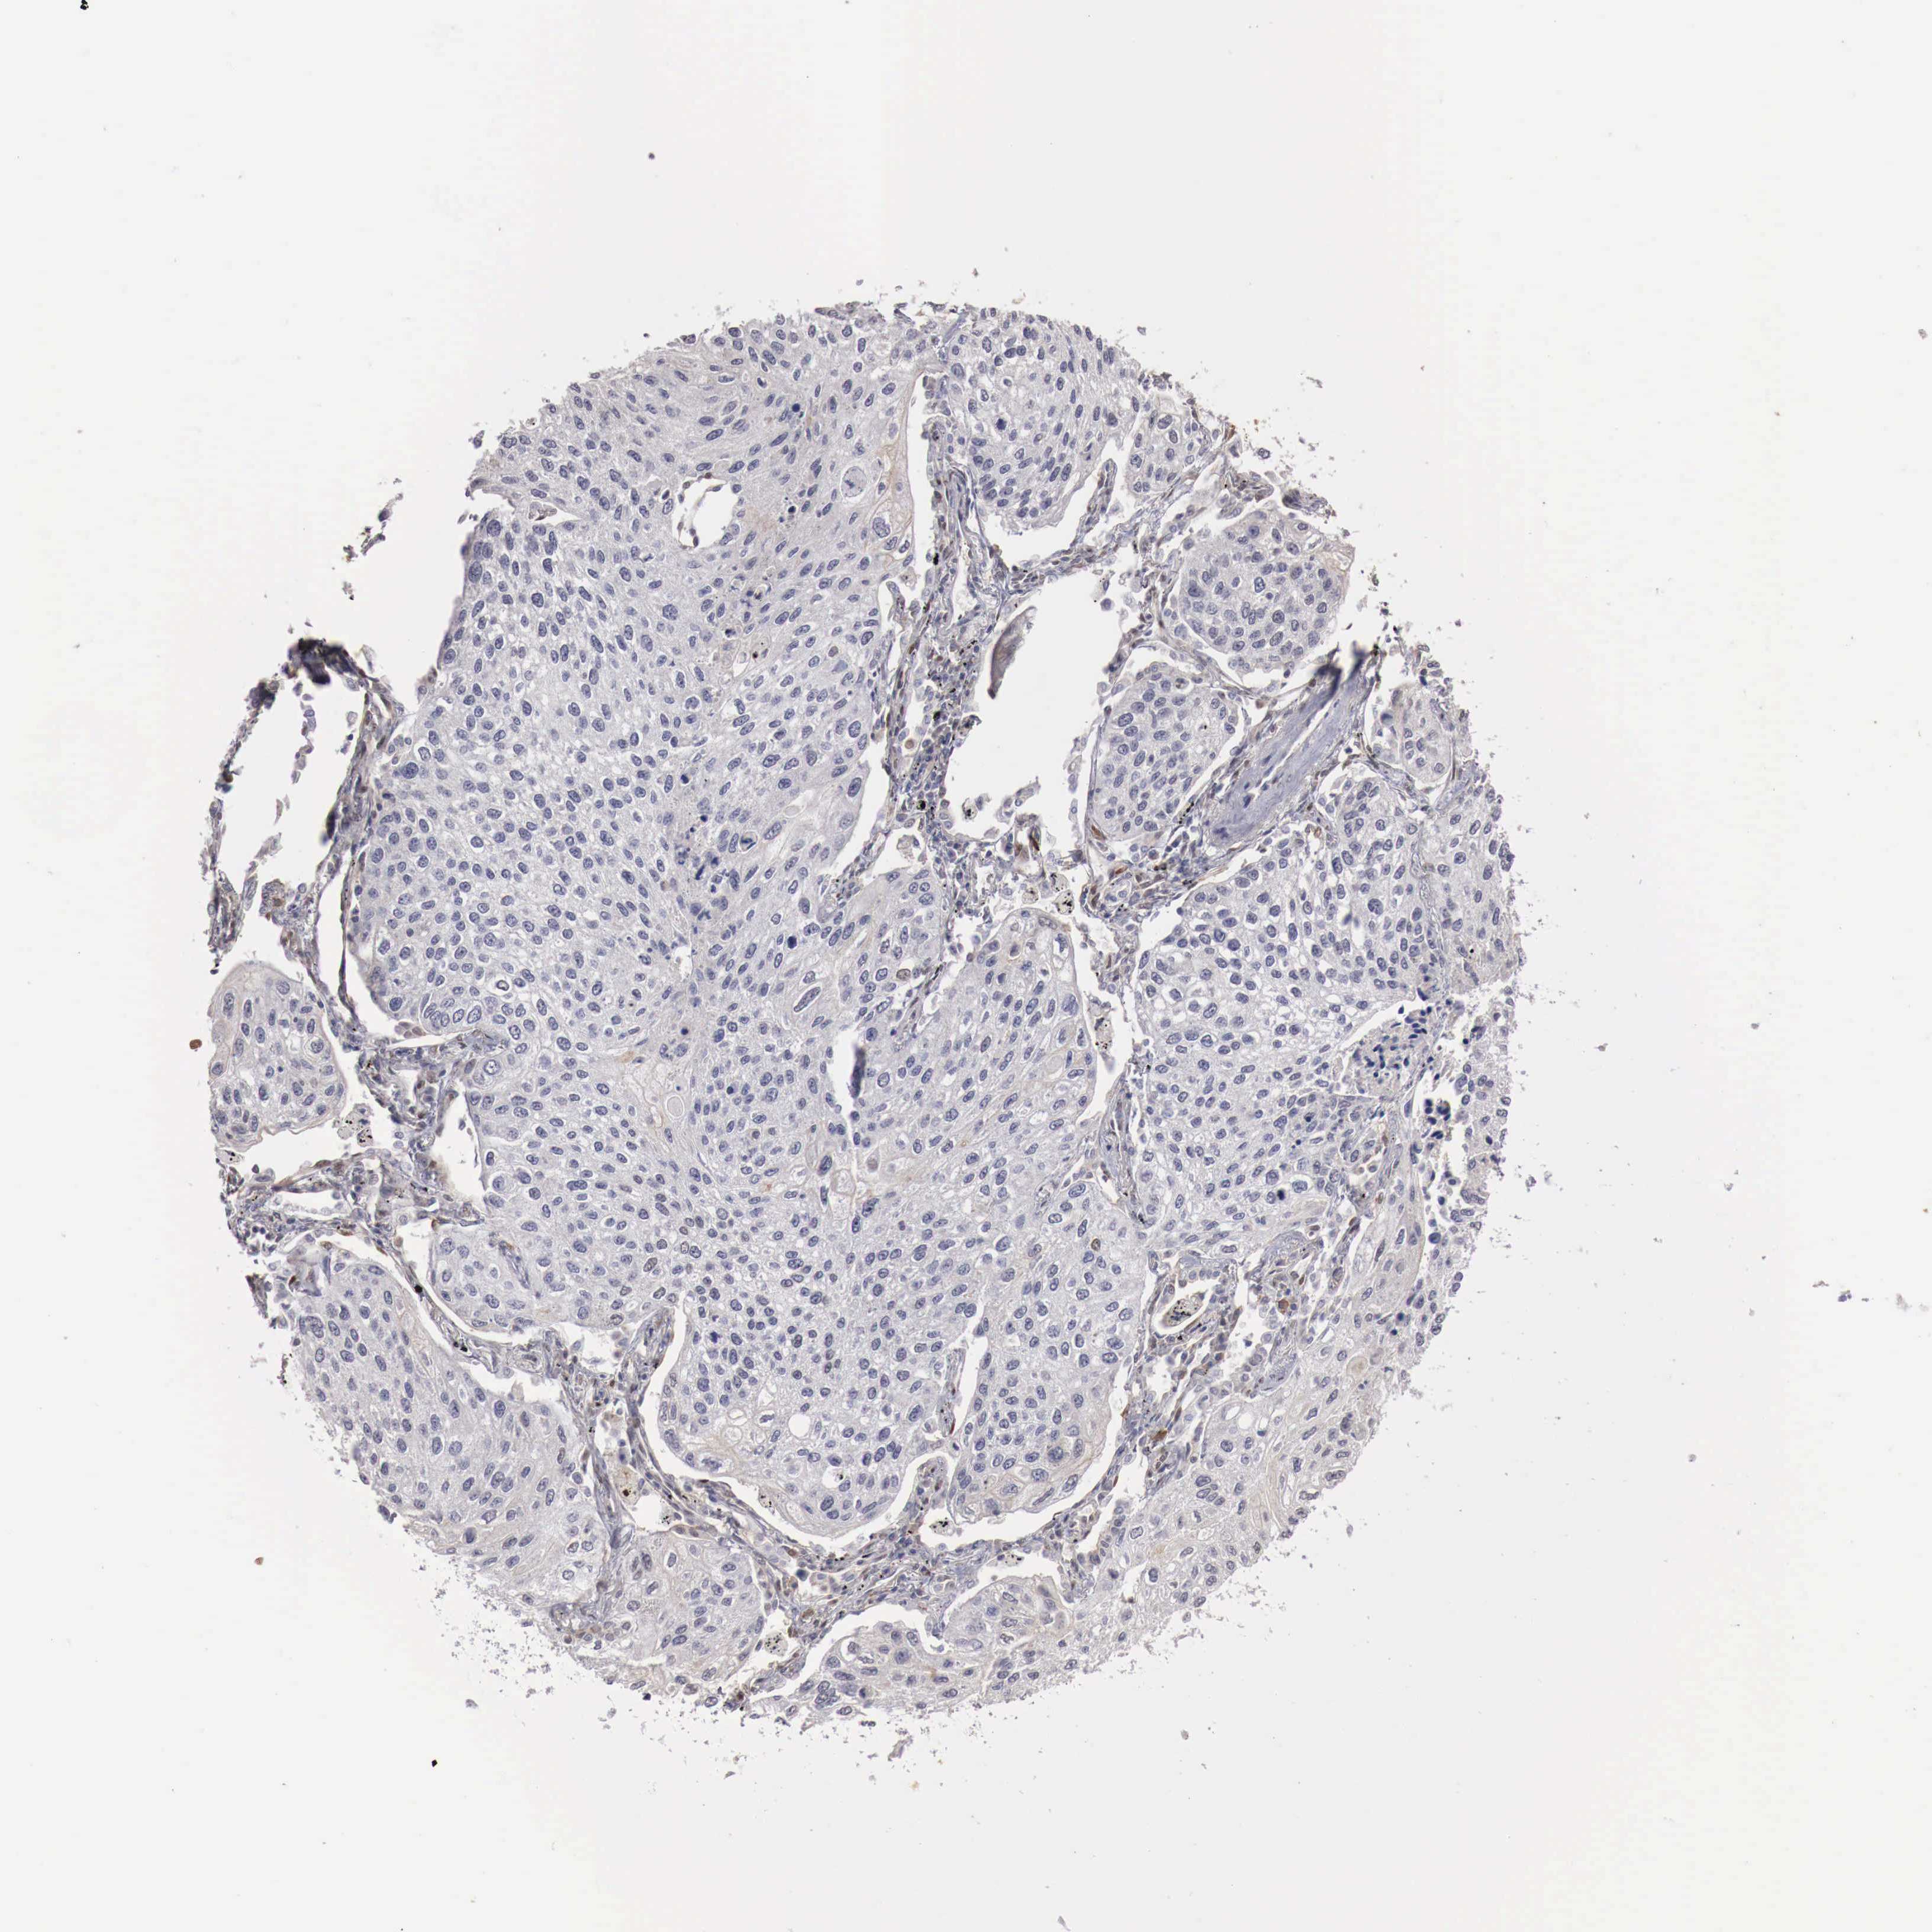

CANCER LUNG CANCER Show tissue menu

KHDRBS3 is not prognostic in Lung Adenocarcinoma (validation)

KHDRBS3 is not prognostic in Lung Squamous Cell Carcinoma (TCGA)